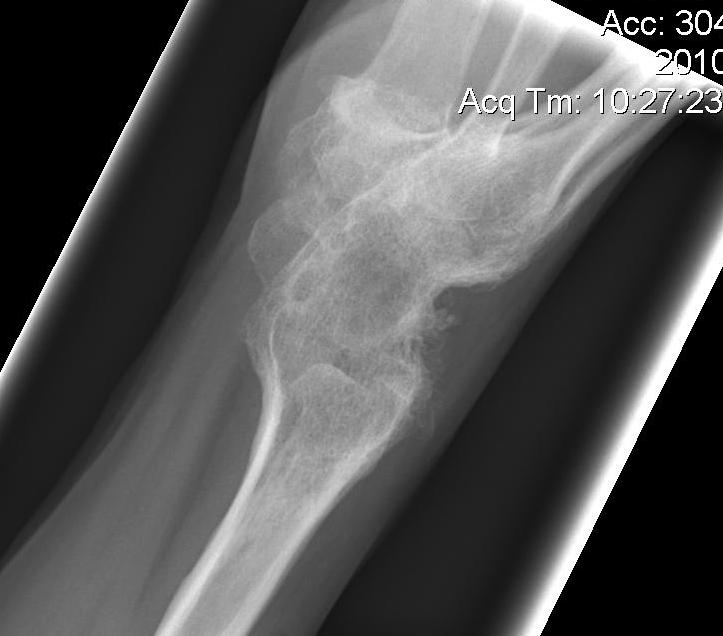

Xray